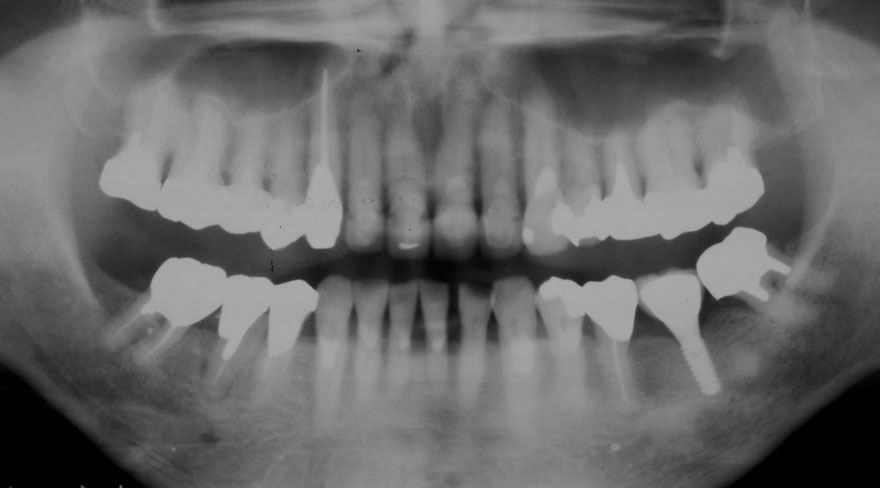

開始年齢 30代

初診時 30歳 女性 平均歯槽骨喪失量:1.46mm

22年後 52歳

平均歯槽骨喪失量:1.55mm

22年間喪失量:-0.09mm

年間喪失速度:-0.004mm

(ケア頻度:1.76ヵ月ごと)